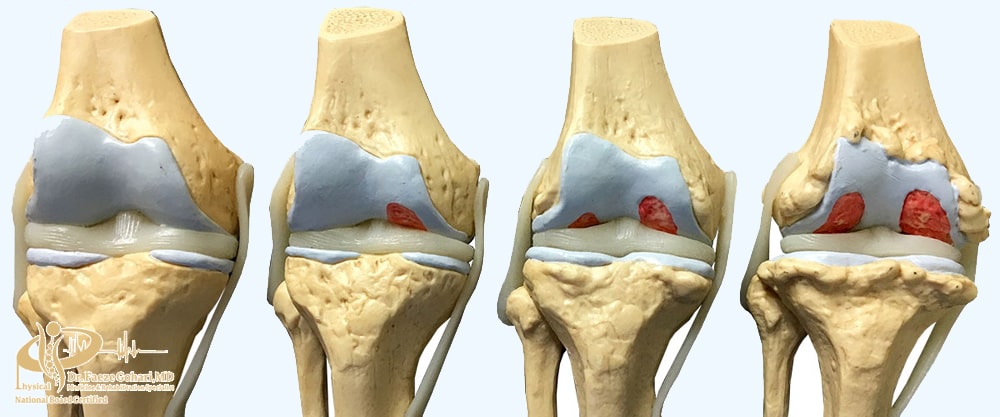

آرتروز زانو

PRP با کاهش التهاب مزمن، تحریک سلولهای غضروفساز و تقویت بازسازی بافت مفصلی، محیط مفصل را از حالت تخریبی خارج کرده و شرایط را برای ترمیم حفظ میکند. این کار میتواند روند فرسایش تدریجی غضروف را آهستهتر کند. هم چنین استفاده از مکملهایی مانند قرص غضروفساز زانو نیز میتواند به حمایت از سلامت غضروف و بهبود انعطافپذیری مفصل کمک کند. البته باید گفت که PRP بیماری آرتروز را متوقف یا درمان نمیکند، اما میتواند سرعت پیشرفت آن را کاهش دهد و نیاز به جراحی را به تأخیر بیندازد.

بر اساس مطالعهای با ۵۱۷ بیمار، پس از سه نوبت تزریق پی آر پی، ۶۲٪ بیماران بهبود قابلتوجهی در درد و عملکرد زانو نشان دادند. اثربخشی در آرتروز خفیف ۷۵٪، متوسط ۶۶٪ و شدید ۵۰٪ بود که نشاندهنده تأثیر بیشتر پی آر پی در مراحل اولیه آرتروز است.